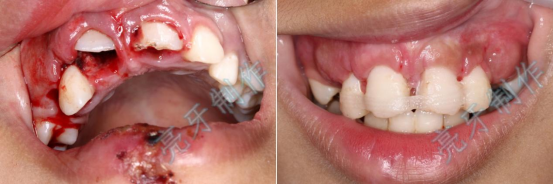

病例一:上门牙外伤,牙齿脱落;再植治疗3个月后,恢复良好。

病例二:外伤导致上牙槽骨骨折,而且上下两颗门牙脱位;通过治疗,上下两颗门牙均恢复原来位置,而且和之前一样结实。